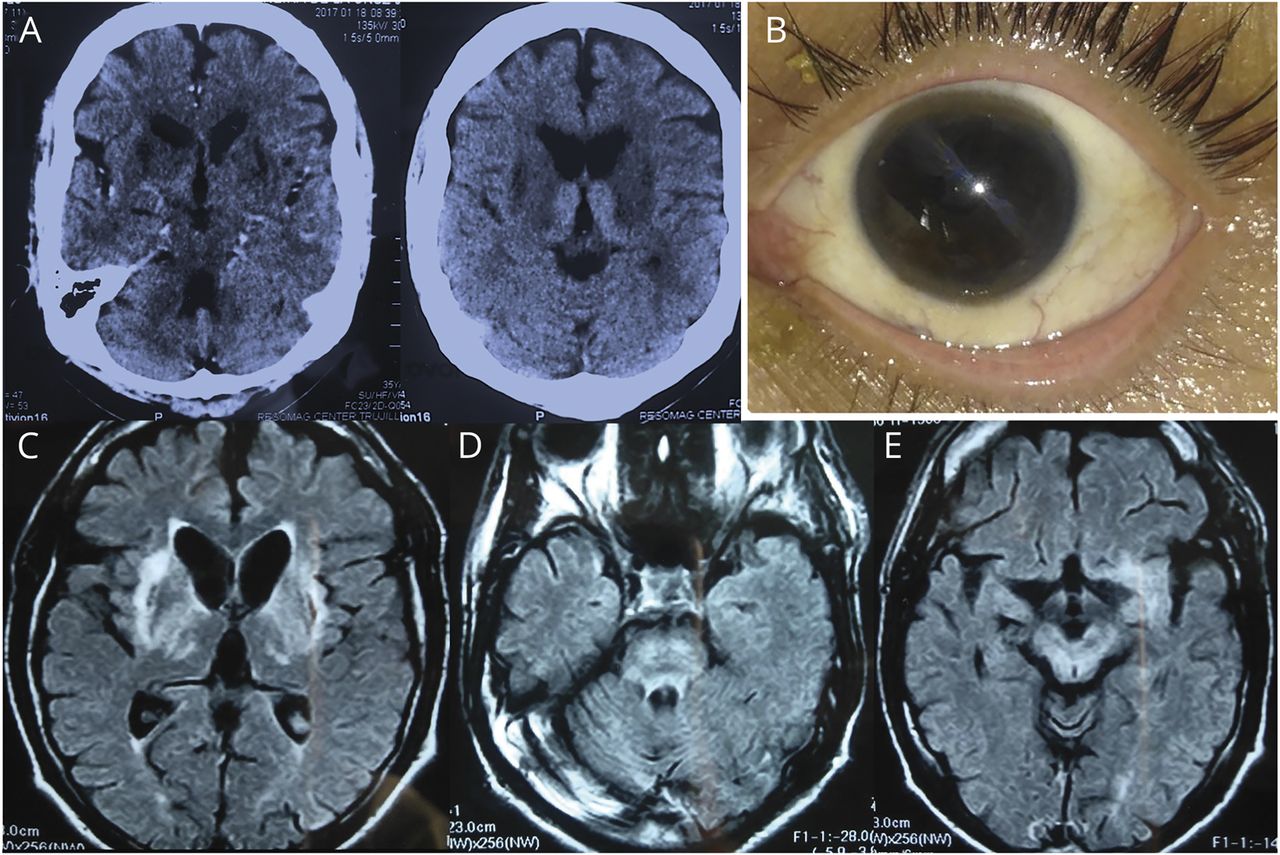

(一)头部CT显示hypodense壳核和高密度的丘脑内侧。(B)眼睛Kayser-Fleischer戒指。棕色环包围了虹膜,由于角膜铜沉积。(汉英)轴向fluid-attenuated反转恢复大脑核磁共振表明异构hyperintense神经节(C)信号,脑桥(D,“面对熊猫宝宝”),和中脑(E,大熊猫“面子”)。